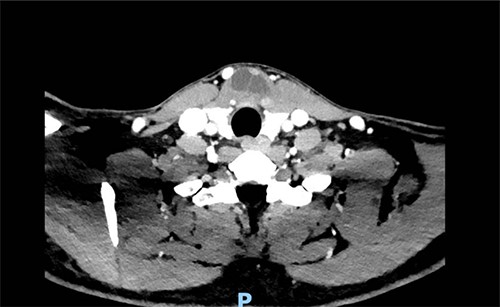

Two months ago, the patient began with a volume increasing mass in the anterior side of the neck, without any added symptoms. The patient visited a physician who asked for a thyroid ultrasound, which was performed on august 16th of the present year. The study showed a midline-neck heterogeneous cystic mass. The follow-up plan included a contrast-enhanced computer tomography scan, to analyze the possibility of a neo proliferative mass, as the radiology specialist suggested. The scan was performed 2 days later, and it revealed a solid cystic tumor, with multiple septa, localized on the midline adjacent to the thyroid gland and its pyramidal lobe (Fig. 5). The histopathology report suggested a thyroglossal duct cyst related to a papillary-type thyroid cancer (Fig. 6).

Solid cystic tumor, with multiple septa, localized on the midline adjacent to the thyroid gland.